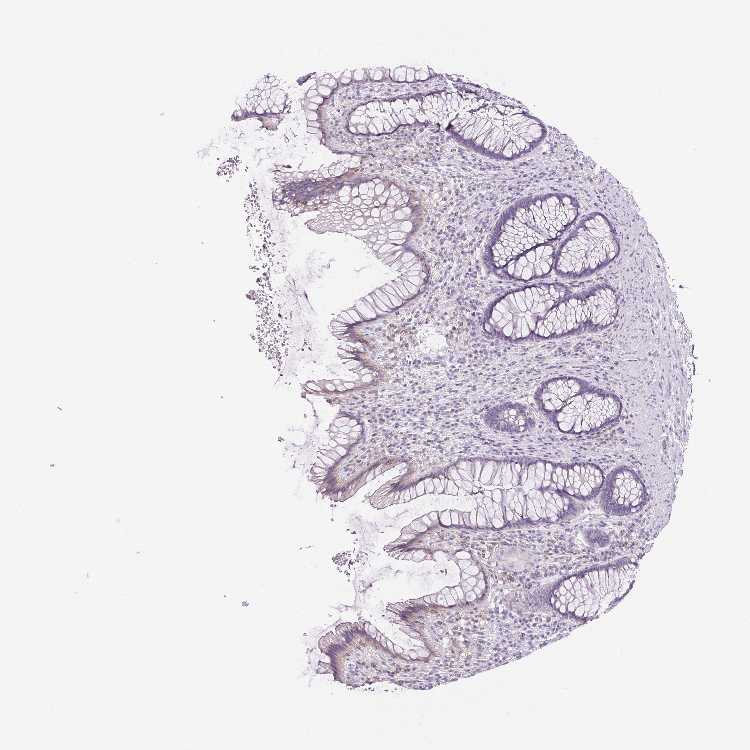

S100A2